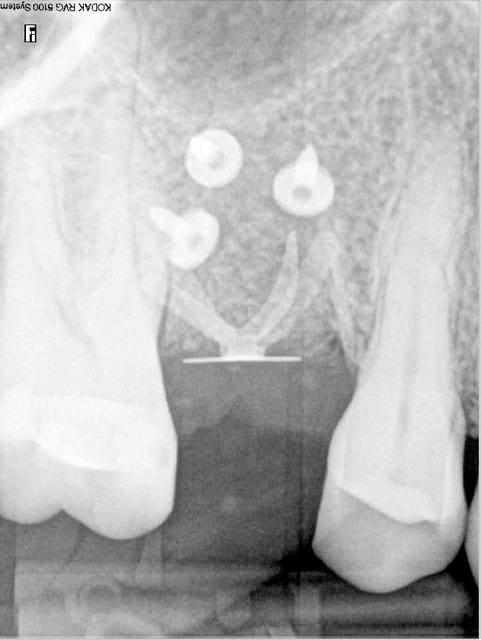

Bravo D57 pour ta chirurgie de reconstruction avec le systeme Fast.

mais j'ai quelques remarques:

1. tes vis ne sont pas positionnées comme il faut.

2. tes vis sont trop enfouies

3. tes sutures ne sont pas assez profondes. comme je te le disais à l'ADF, tu dois être à au moins 1 cm de la berge.

4. Donc, je peux te le dire d'avance: le résultat sera moyen. Je t'avais proposé de préparer ensemble le protocole chirrugical. dommmage.